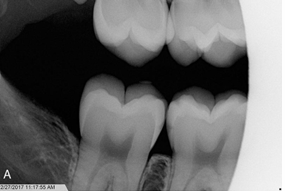

What is the problem with this Elongation X-ray?

Inadequate vertical angulation, Long, distorted teeth

How would you resolve this Elongation X-ray?

Move PID